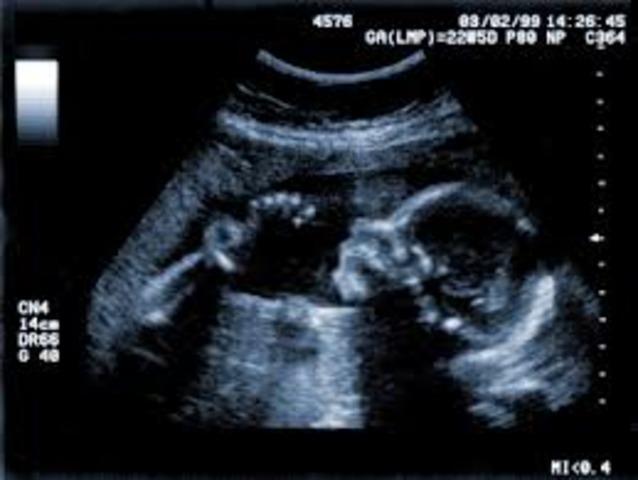

About 3 inch, It can suck its thumb, swallow hiccup and move around. Its facial features become clearer.

About 6-7 inch. Hair, eyelashes, and eyebrows appear, teeth continue to develop, organs are maturing and it becomes more active.